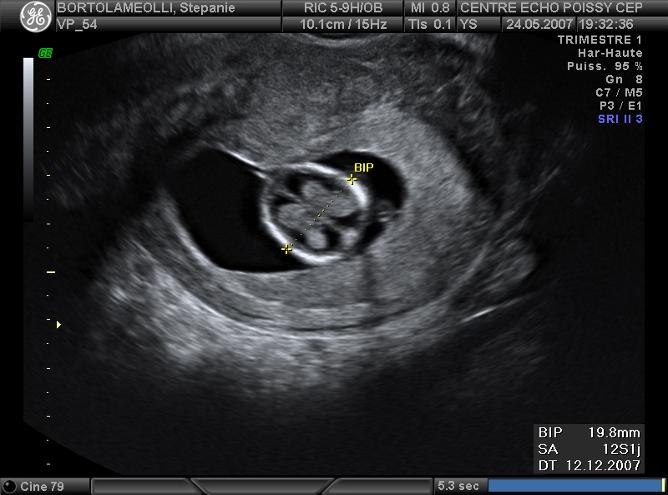

Echographies